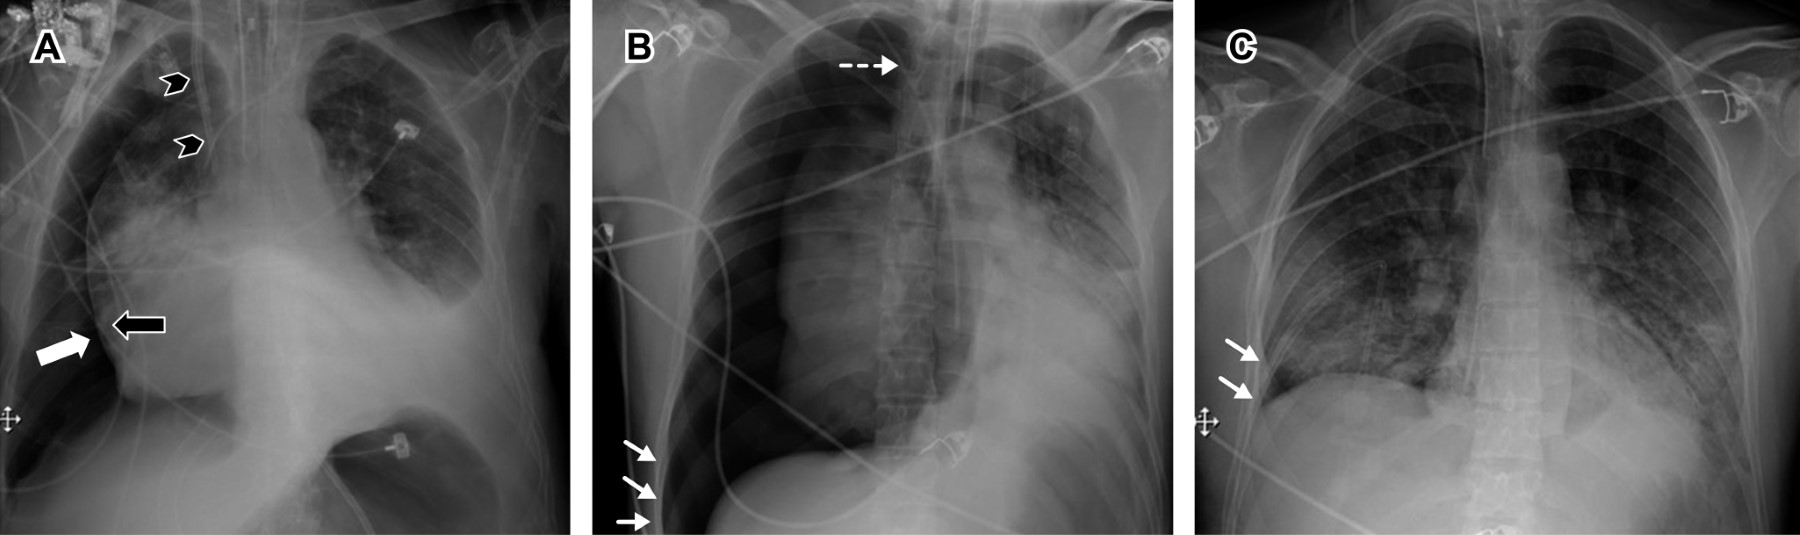

La situación ideal del tubo endotraqueal está dada por la distancia entre el extremo distal y la carina; en la literatura se considera que la posición correcta es de entre 3 y 7 cm superior a ésta, con el cuello en posición neutra, ya que con la extensión o la flexión del mismo es posible modificar la altura de la punta del tubo de hasta 2 cm de diferencia.6-8 También se describe la relación con las cuerdas vocales, considerando una distancia óptima de 3-4 cm inferior a esta estructura para evitar lesión o extubación espontánea.1,3,9 La tomografía y resonancia magnética son las modalidades de imagen ideales para su evaluación.

Cuando no se logra identificar la carina, debemos recordar que normalmente se encuentra entre los cuerpos vertebrales T5 y T7 en 95% de los pacientes.1 Existen otros marcadores anatómicos para determinar si el extremo distal del tubo tiene una posición óptima, y podemos usar de referencia los cuerpos vertebrales T2-T4,6,8 los bordes mediales de las clavículas o la porción caudal del arco aórtico (Figura 1A y B).10

• 1. Intubación selectiva. Si el tubo endotraqueal sobrepasa los marcadores anatómicos antes descritos, existe el riesgo de realizar una intubación bronquial selectiva, generalmente al bronquio principal derecho.3,6 Esto conduce al colapso del pulmón contralateral, e hiperinflación o neumotórax del pulmón ipsilateral (Figura 1C).6